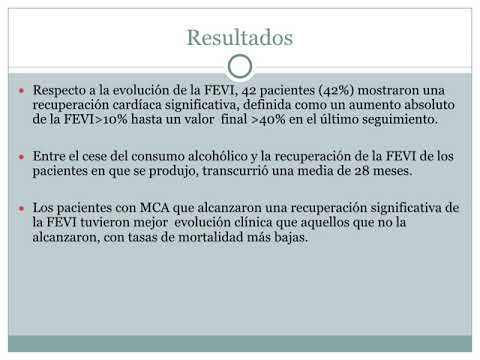

Impacto pronóstico y factores predictores de la recuperación de la fracción de eyección en pacientes con miocardiopatía dilatada alcohólica. Dr. Julián Colla. Residencia de Cardiología- Hospital C. Argerich. Buenos Aires